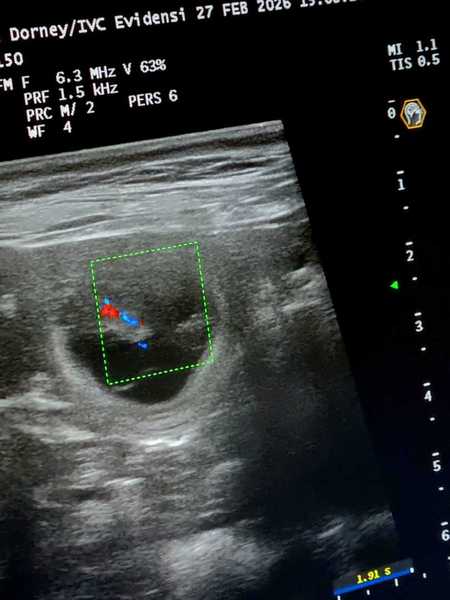

4. Woche     26.Trächtigkeitstag

Heute waren wir zum Ultraschall und was soll ich sagen:

Lani`s Bauch ist voller kleiner Blubberbläschen.

Wir konnten auch schon die kleinen Herzchen schlagen sehen und alles ist für die Zeit bestens entwickelt.